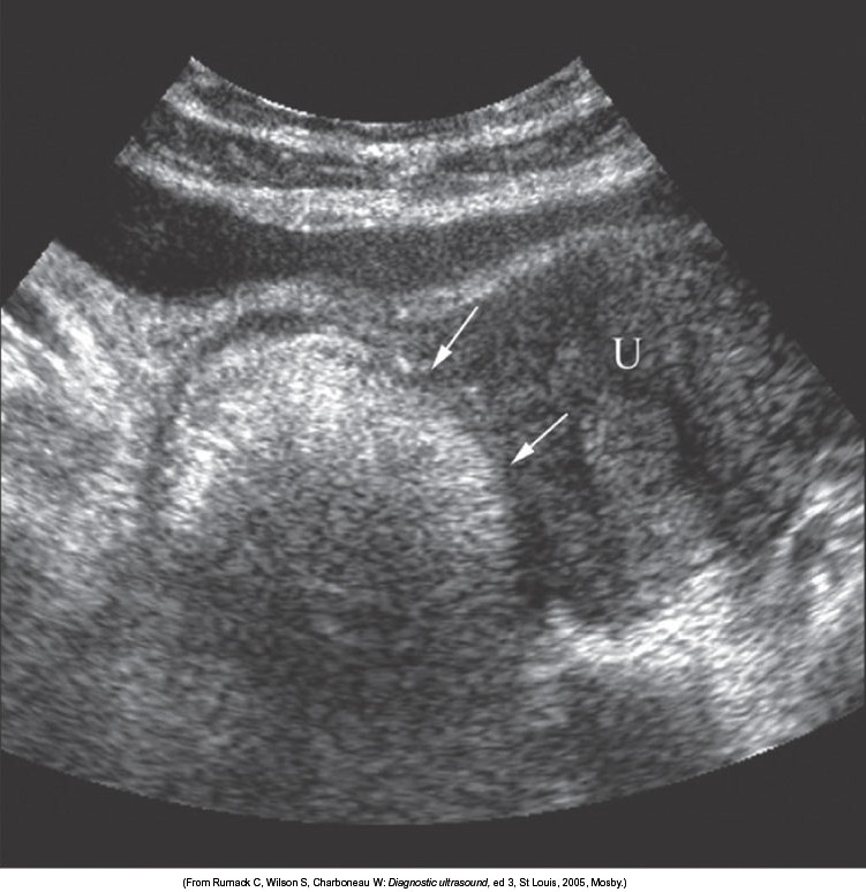

Dermoid Cyst

-tip of the iceburg